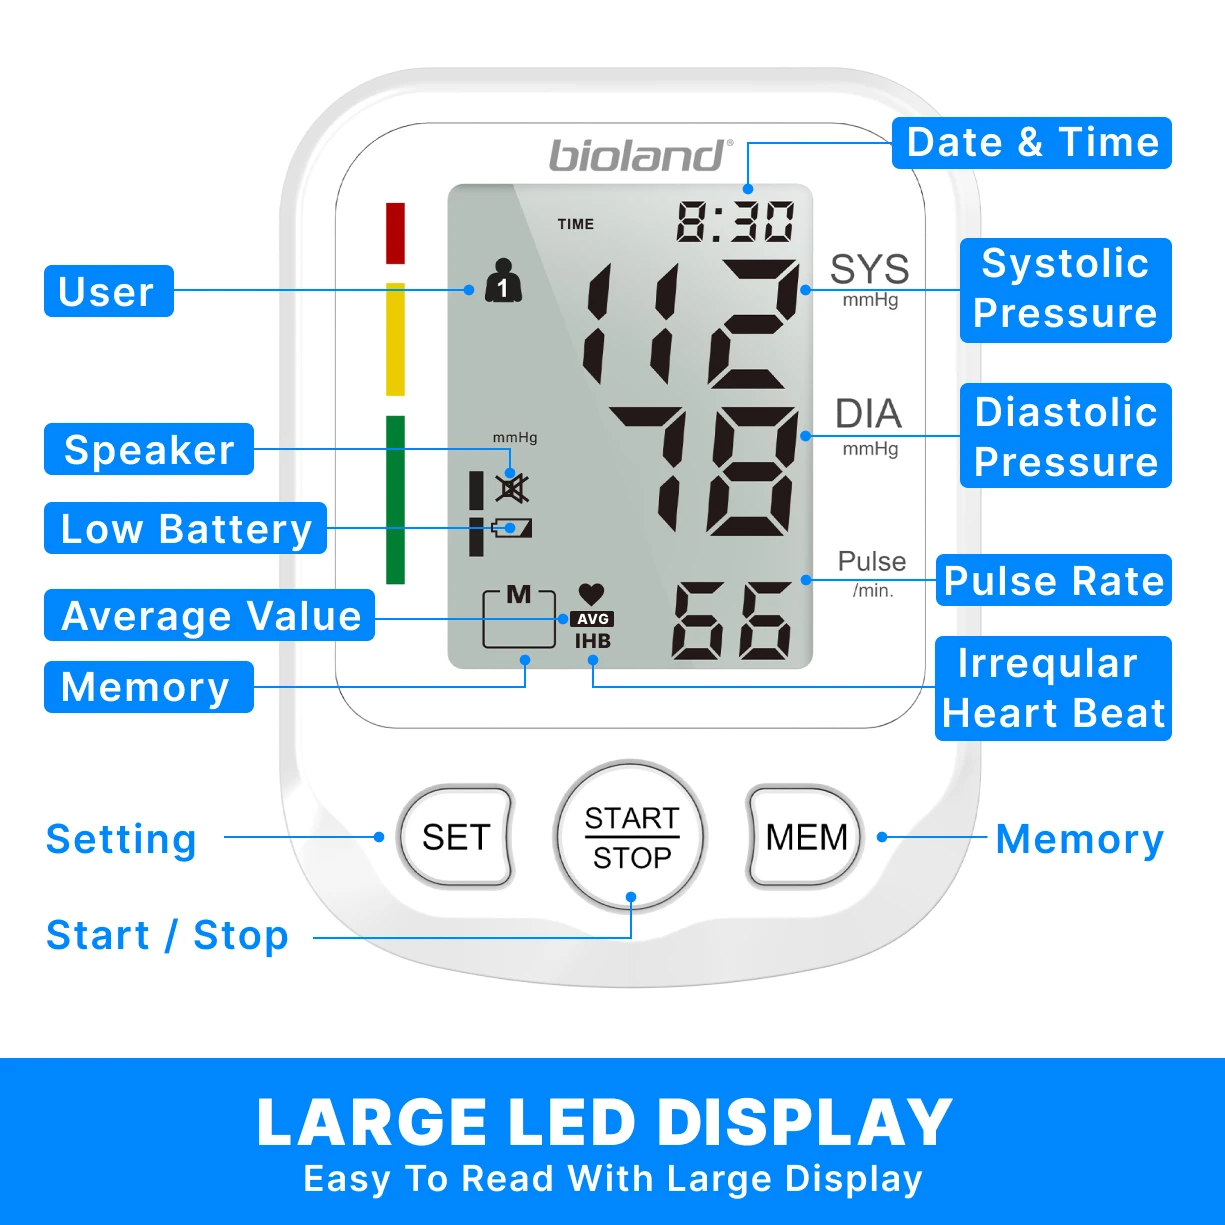

【Large LED Display】

The large LED display with clear and oversized numbers, makes it easy to read your real-time blood pressure and pulse rate. High precision chip of large LED touch screen provides clinically accurate readings, giving the most exact systolic, diastolic pressure and pulse rate data by one touchable button and easy to read the backlist screen with multi-colored LED indicator lights.

【120 Memory for 2 Users】

This BP unit can monitor 2 users together, store 120 readings with date & time stamps for each displays the average of last 3 readings, includes irregular heartbeat detection. Helps users to easily track their health, blood pressure and heart rate according to the specific time and date.

Features:

1.HD screen display;High quality acrylic lenses

2.Irregular heartbeat detection (IHB function)

3.Blood pressure classification (WHO) indicator

4.2*120 groups memory function

5.Cuff tightness detection (22-42cm cuff)

6.Smart pressure; Overvoltage protection

7.Voice reporting(With English talking voice)

8.Low power prompt

9.Average of last 3 Memories

【Blood Pressure&Heartbeat Indicator】

A coded indicator for blood pressure. The irregular heartbeat symbol will show up when an irregular heartbeat is detected. When a specific error occurs in the product, the cause of the error can be determined by comparing the error symbol with the manual.